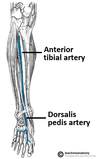

What is this muscle

The Rhomboid minor